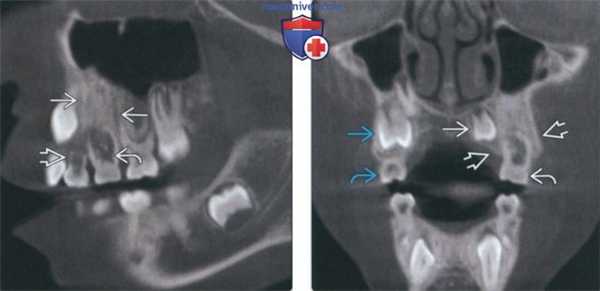

(Слева) На сагиттальной реформатированной КЛКТ у восьмилетней девочки определяется плотности верхней челюсти слева с наличием вытянутых просветлении, вероятно, представляющих собой питающие каналы. Определяется патологическая резорбция временного клыка и первого моляра. Изменения сопоставимы с сегментарной верхнечелюстной одонтодисплазией (СВО).

(Справа) На корональной КЛКТ у этой же пациентки определяется ↑ ширины верхней челюсти слева. Формирующийся первый левый премоляр смещен в сторону неба и имеет меньший размер, чем правый. Второй премоляр отсутствует. Первый временный моляр слева больше, чем справа.

(Слева) На кадрированной панорамной рентгенограмме у женщины 26 лет определяется повышение плотности альвеолярной кости в области премоляров верхней челюсти справа. Визуализируется просветление между первым моляром и клыком, подозрительное на расщелину. О наличии расщелин сообщалось и в других случаях заболевания. Оба премоляра отсутствуют.

(Справа) На фотографии у этой же пациентки видна расщелина угла рта на фоне гиперпигментации лица. Эти нарушения часто сочетаются с СВО. Также наблюдается гипертрихоз.